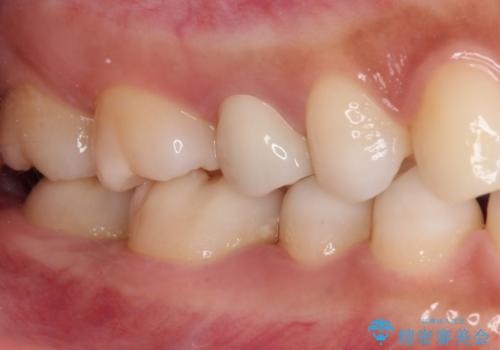

どちらの歯も痛みなどの症状はなく、治療後も異常所見なく経過をたどっています。

上顎大臼歯は向かい合った人から見えることはほとんどないため、切削量が少なく、適合の良いゴールドインレーが大変おすすめとなります。